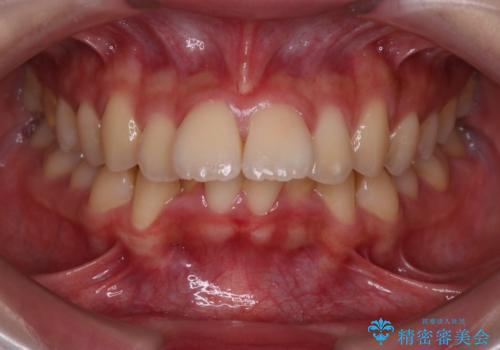

- 前歯の突出を主訴に来院されました。

アンカースクリューとインビザラインを用いて遠心移動を行うことでできる限り前歯を下げて叢生の改善を行いました。